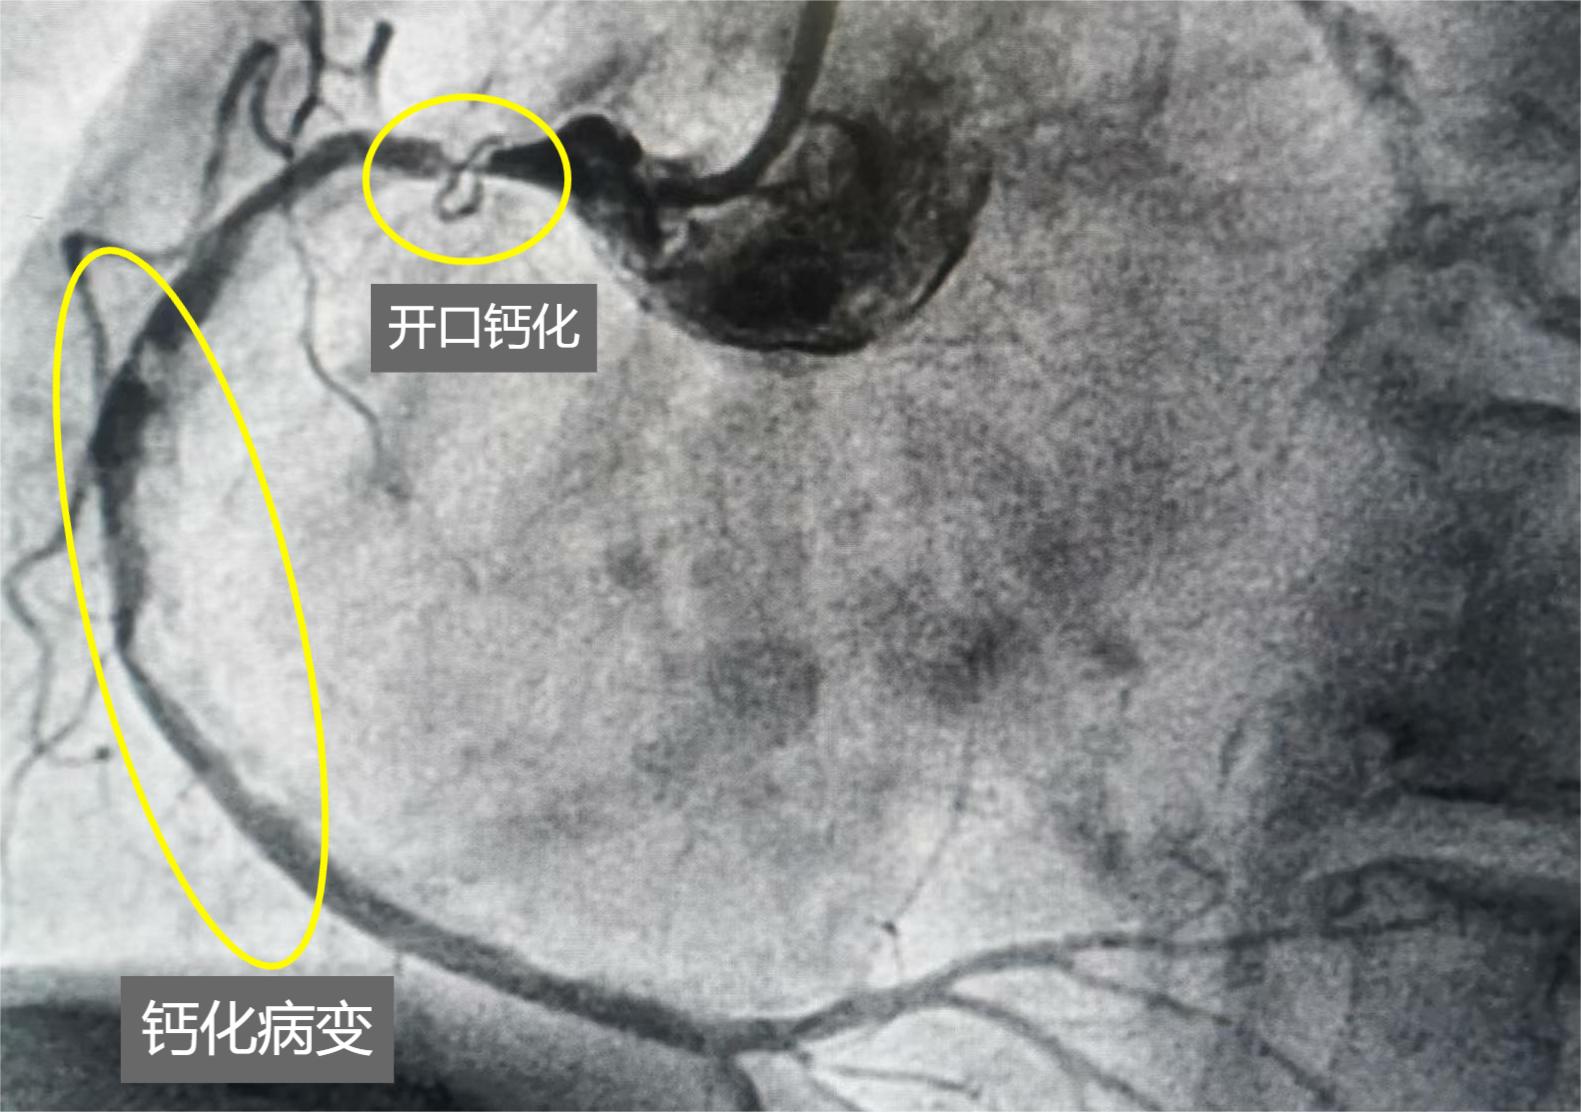

74歲王女士的術前血管造影所顯示的鈣化病變。

如今,伴隨著冠脈內旋磨術在哈院的成功開展,無論是醫生還是患者,都從中獲益良多。5月6日上午,耗時91分鐘,心內科副主任醫師韓世飛用1.5毫米旋磨頭反復旋磨開口及近中段鈣化病變,旋磨成功后,先后用3個支架,讓74歲的王女士從冠狀動脈粥樣硬化性心臟病、急性心肌梗死伴隨冠脈嚴重鈣化的危重病情中成功脫險。

74歲王女士右冠開口旋磨。

74歲王女士的鈣化病變血管旋磨后放入支架,血管恢復的狀況。